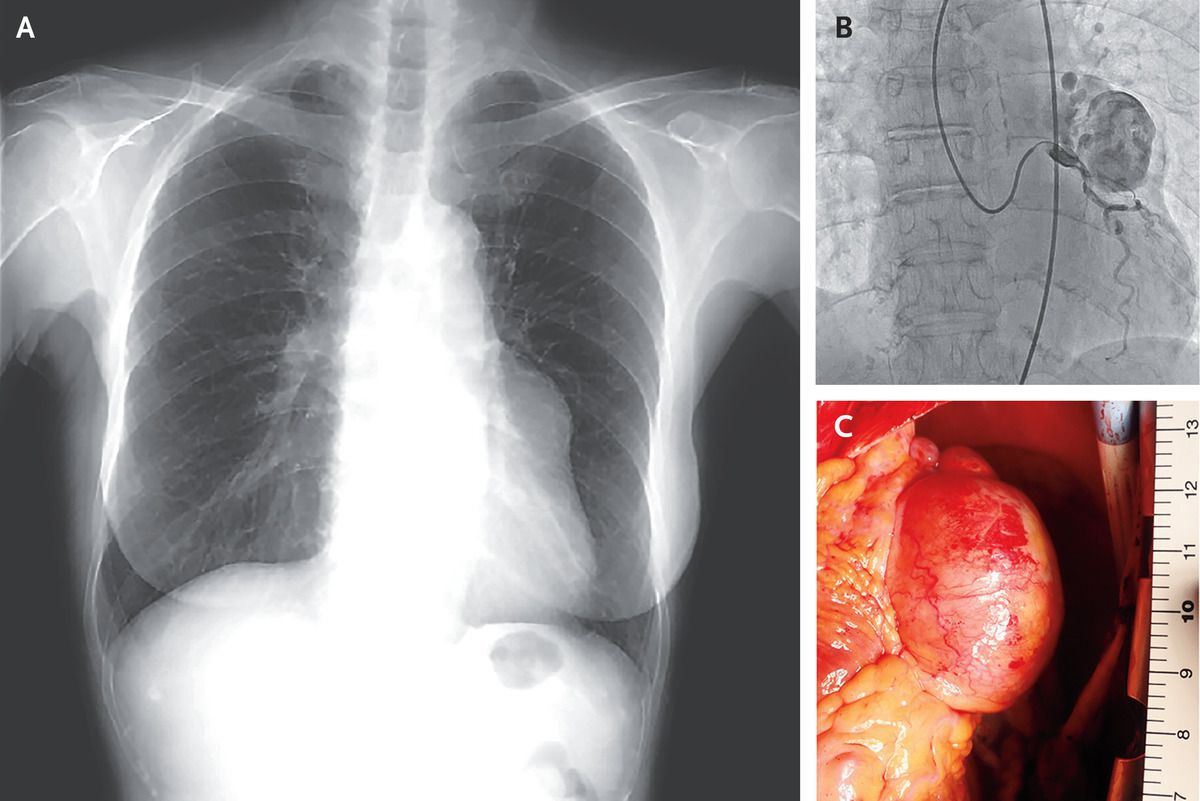

A 79-year-old woman with a history of stroke was referred to the cardiovascular outpatient clinic because of an abnormal radiographic finding along the left border of her heart (Panel A). The patient’s primary care physician had first noted the abnormality 6 years earlier on routine chest radiography. Owing to the patient’s absence of symptoms, the finding was monitored with serial radiographs, which showed that it had gradually increased in size. The cardiac examination was normal. Coronary computed tomography revealed an aneurysm measuring 45 mm in the greatest dimension arising from the left coronary artery — a finding that was consistent with a diagnosis of giant (measuring >20 mm in the greatest dimension) coronary-artery aneurysm. Subsequent cardiac catheterization showed blood flowing from the left coronary artery into the aneurysm and also into the pulmonary artery through a fistula (Panel B and video). Cardiac surgery involving ligation and plication of the aneurysm (Panel C) and closure of the fistula was performed. Giant coronary-artery aneurysms are often incidental and asymptomatic findings, but complications such as thrombosis, distal embolization, and rupture have been reported. The aneurysms are typically managed surgically, even in asymptomatic patients. The patient did well after surgery and was discharged 16 days later.